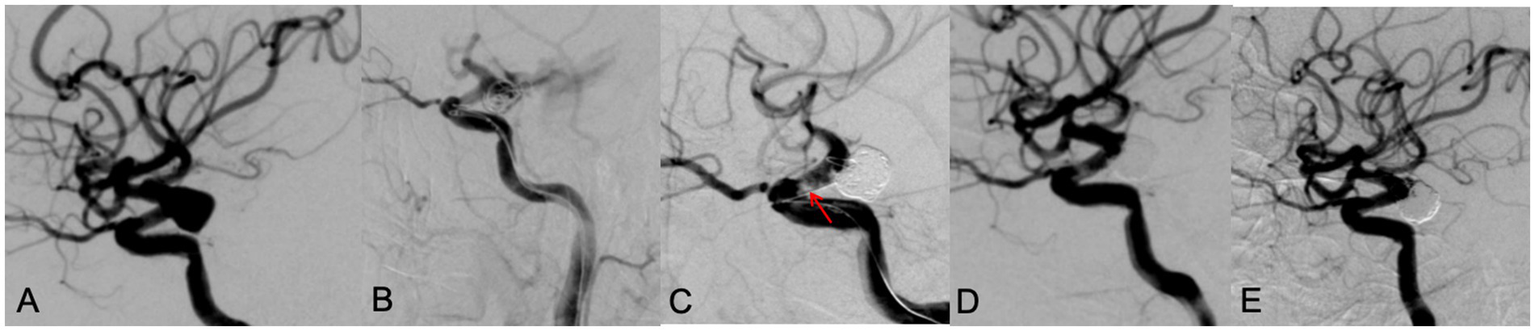

All patients successfully completed SAC for WNIA, and the technical success rate was 100%. Immediate postembolization angiography showed that in the Neuroform Atlas group, 22 aneurysms (81.5%, 22/27) achieved MRRC Class I, 5 aneurysms (18.5%, 5/27) achieved Class II, and 0 aneurysms (0%) achieved Class III. In the LVIS group, 25 aneurysms (73.5%, 25/34) achieved MRRC Class I, 9 aneurysms (26.5%, 9/34) achieved Class II, and 0 aneurysms (0%) achieved Class III. There was no significant difference in the initial obliteration class between the two groups (p = 0.549) (Table 2). Representative cases of the Atlas group and LVIS group were shown in Figures 1, 2, respectively.

Intraoperative complications occurred in two patients, both of them were in the LVIS group. One patient had a left posterior communicating artery aneurysm. During the procedure, the aneurysm ruptured. Immediately, emergent protamine reversal of heparin was applied, and multiple ev3 coils were packed through another microcatheter until angiography showed no contrast extravasation, however, an in-stent thrombosis was noted. Tirofiban was then administered. The final angiography showed patent vessels, disappeared in-stent thrombosis, and occlusion of the aneurysm (Figure 3). The patient recovered well. The second patient had a left vertebral artery wide-neck aneurysm. During LVIS stent-assisted embolization, the aneurysm ruptured. Rapid coil packing was performed, and as contrast extravasation persisted, finally the parent artery and the aneurysm were all occluded. Because of the patent contralateral vertebral artery, the patient recovered well postoperatively.

Figure 3. A 65 year old male patient with diplopia for 3 weeks. DSA showed a left posterior communicating aneurysm with wide neck (A). During the LVIS stent assisting embolization, the aneurysm ruptured with contrast leakage (B). After rapid dense coil packing, contrast leakage was stopped, however, an in-stent thrombosis (red arrow) was observed (C). After intravenous use of tirofiban, thrombosis disappeared, the aneurysm was occluded with MRRC grade 1 (D). A 9 months’ follow-up DSA examination showed the aneurysm was occluded well with MRRC grade 1 (E).